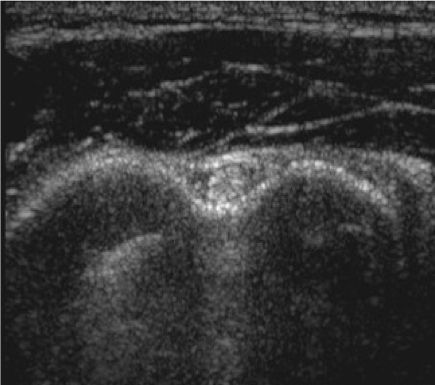

Bicipital tendinitis is a condition caused by inflammation of the long head of the biceps muscle’s tendon. It’s commonly caused by sudden overuse of the muscle and rotator cuff pathology such as muscle or tendon tears, chronic impingement, multidirectional shoulder instability, calcifications, and deconditioning. Signs in physical examination correlating with bicipital tendinitis are pain at the bicipital groove and a positive provocative test such as Speed’s test and Yergason’s test, although studies have shown that their sensitivity might be poor.1